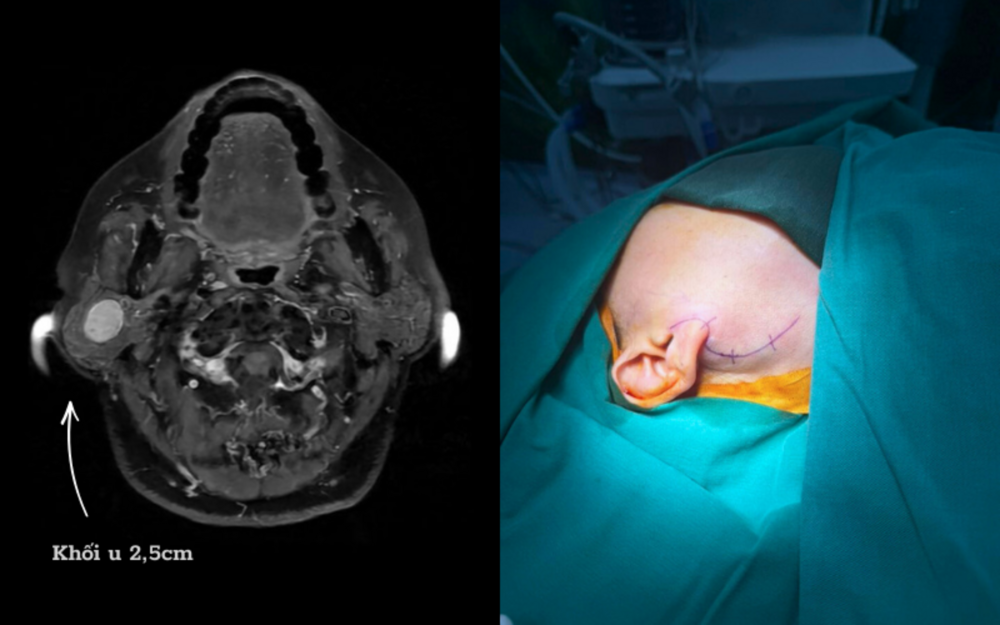

Nguy Cơ Liệt Mặt